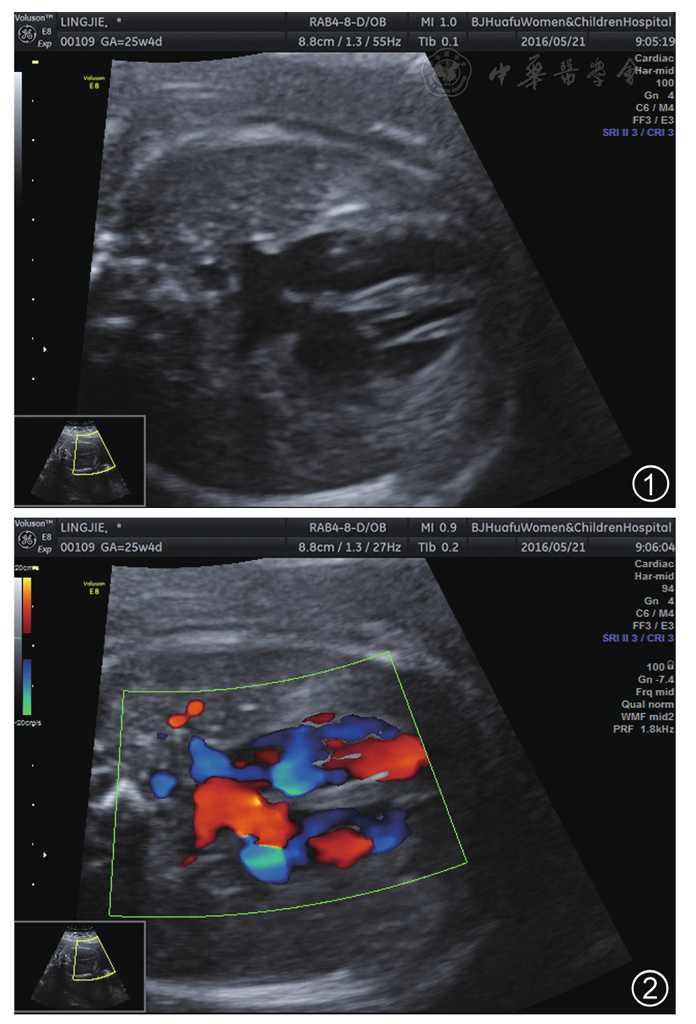

图2 彩色多普勒血流成像示卵圆孔右向左分流